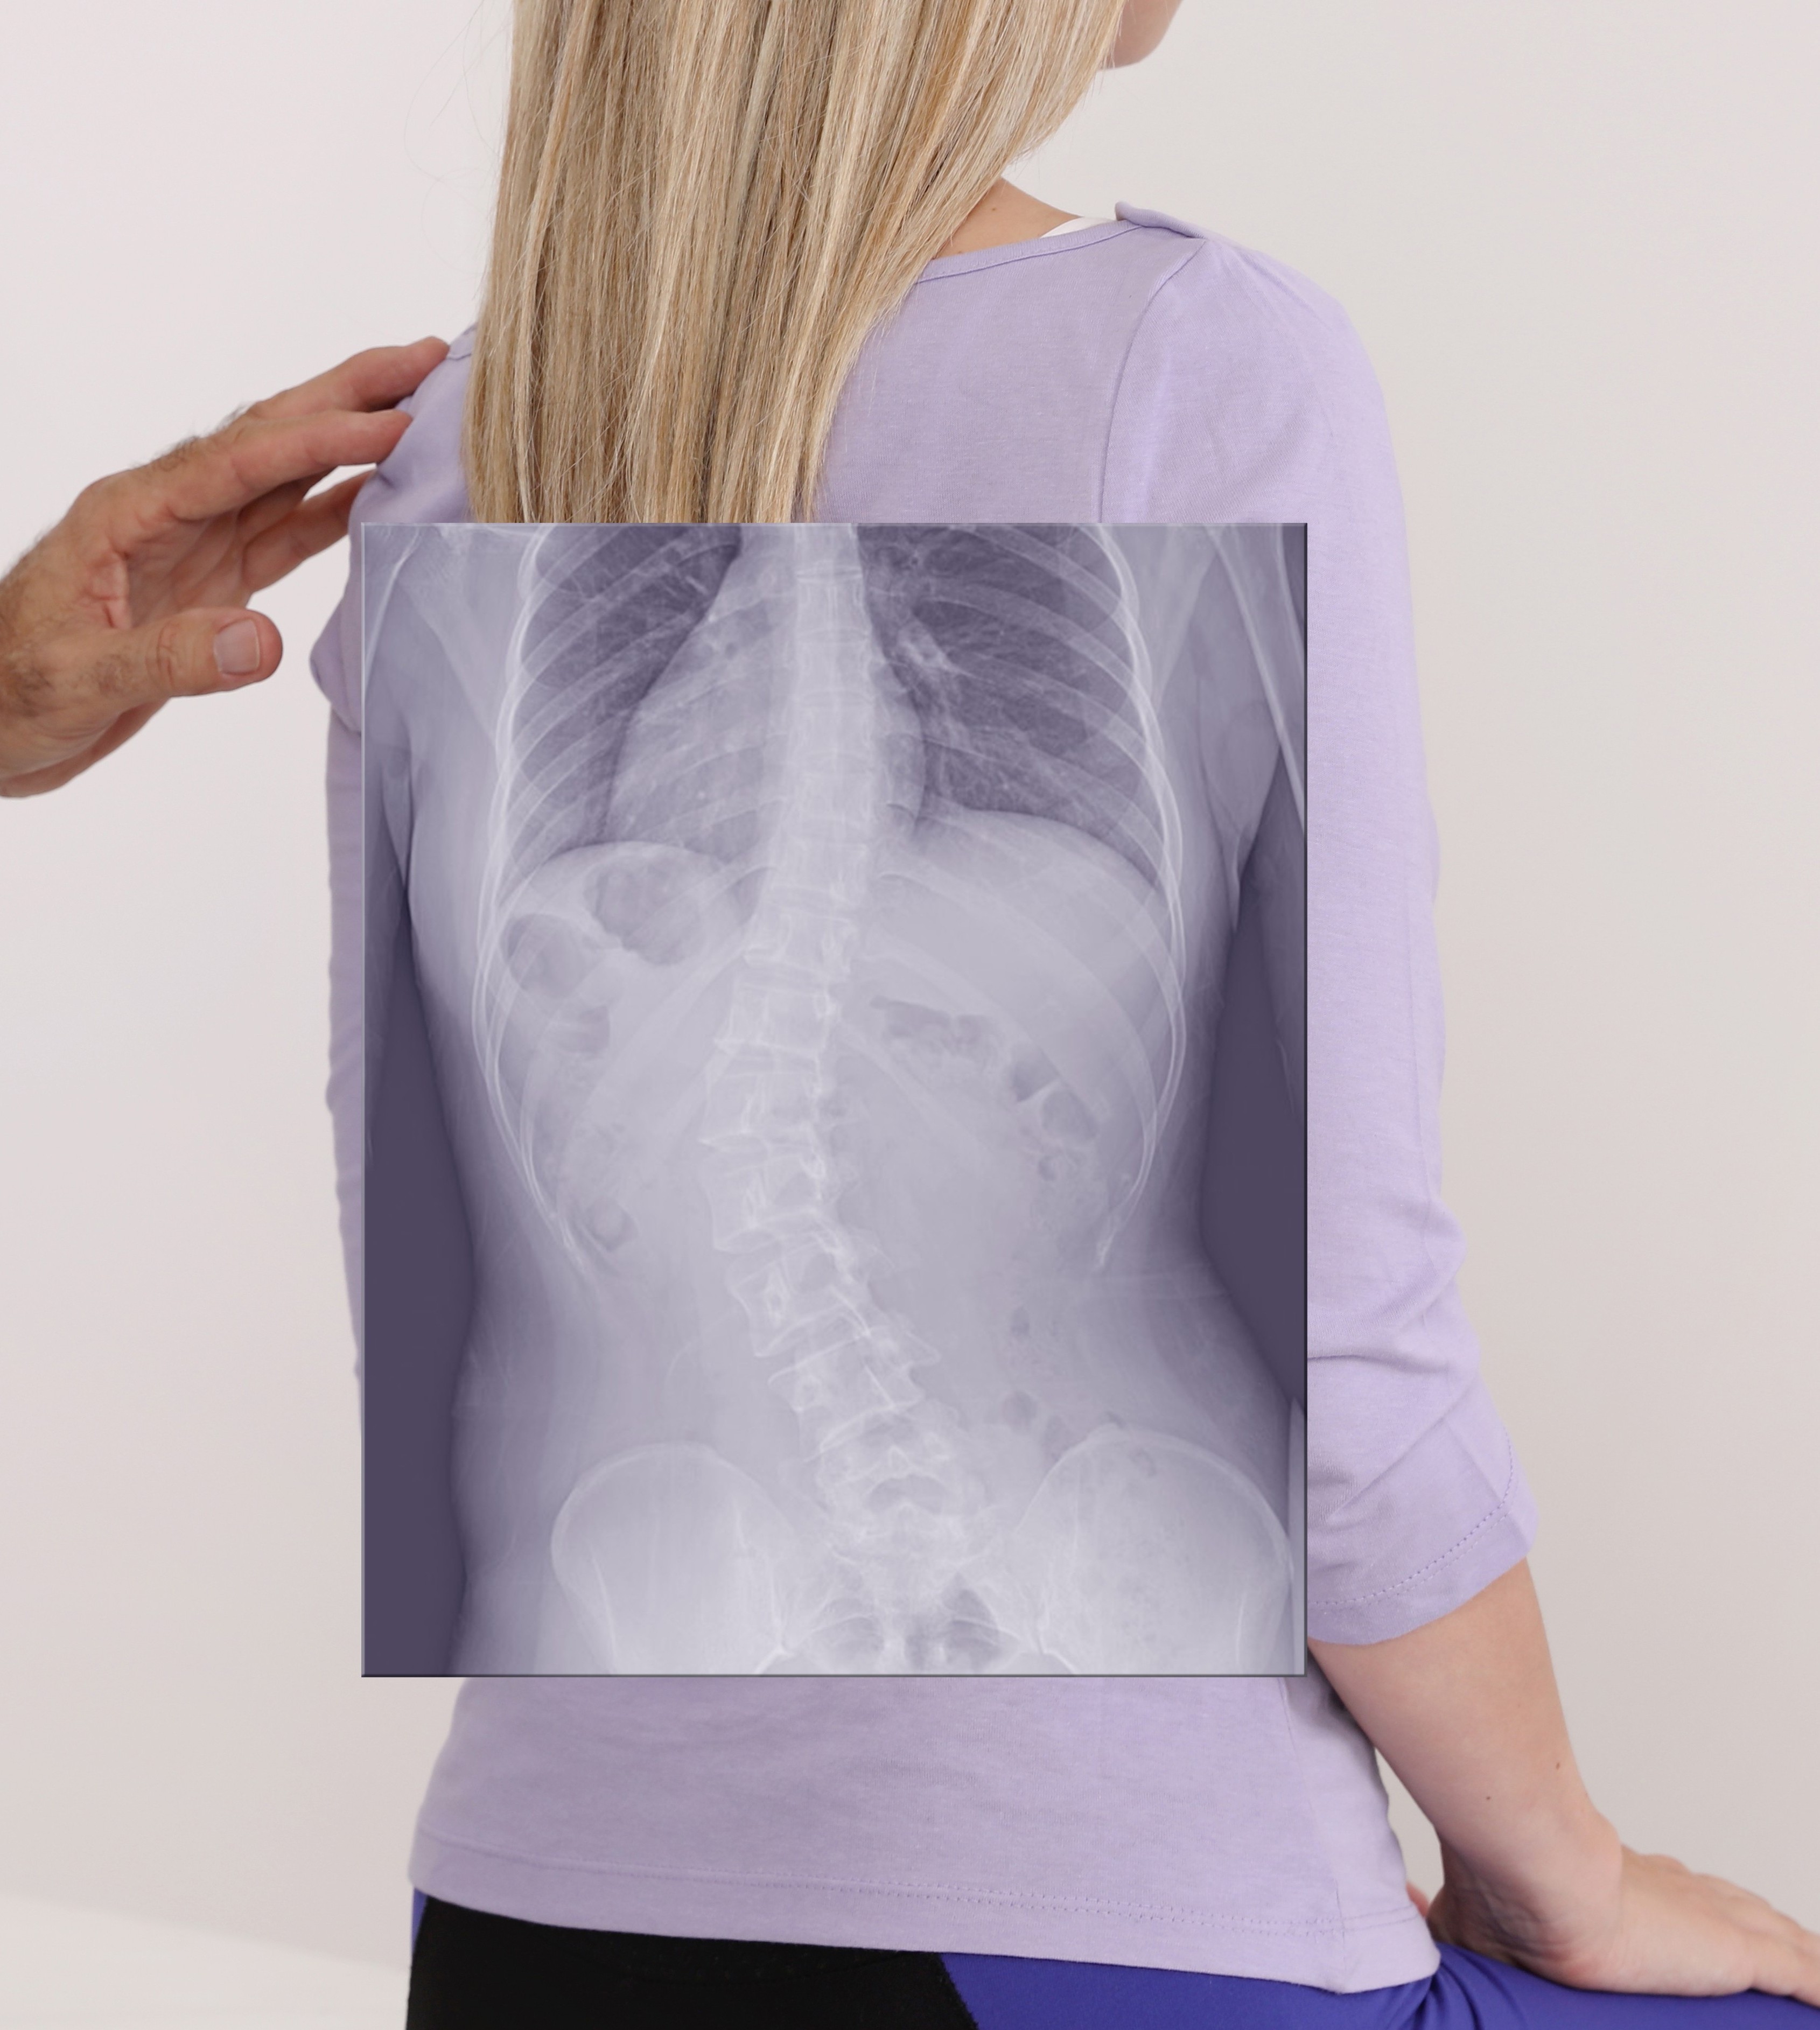

Detection

Early detection: Starting the conversation.